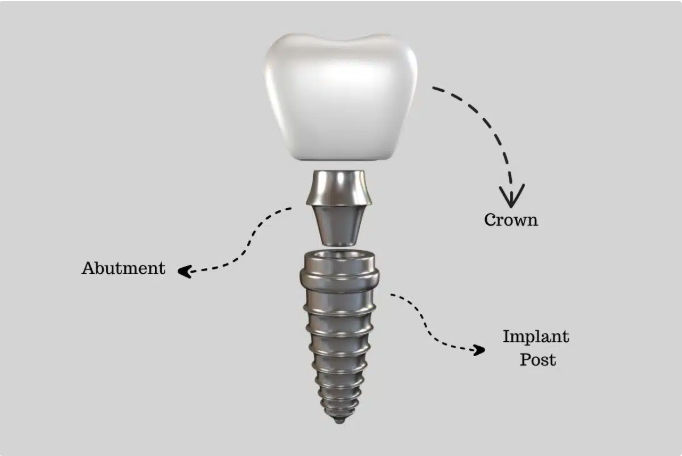

ایمپلنت دندان، یک ساختار تیتانیومی یا زیرکونیایی است که به عنوان ریشه مصنوعی در استخوان فک کاشته میشود. این فرآیند شامل سه بخش اصلی است:

- پایه ایمپلنت (پیچ تیتانیومی): که در استخوان فک قرار میگیرد و با استخوان جوش میخورد (فرآیندی به نام osseointegration).

- اباتمنت: قطعهای که پایه را به روکش متصل میکند.

- روکش (تاج دندان): که شبیه دندان طبیعی است و بر روی اباتمنت قرار میگیرد.